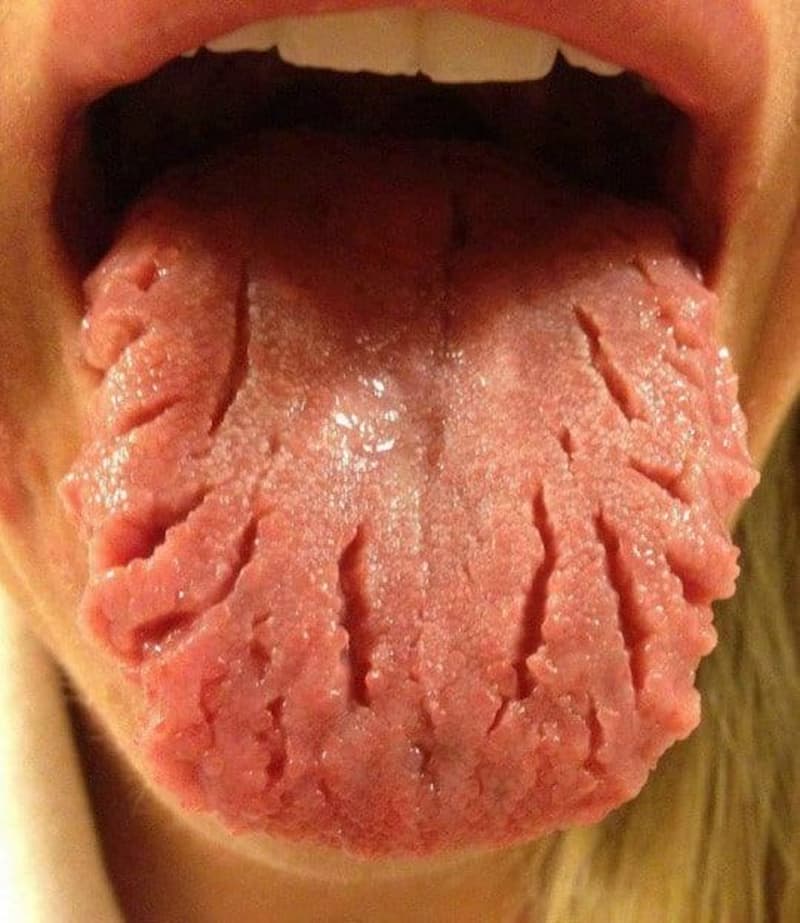

En el ámbito de la odontología y la salud dental, seguro que muchas veces has escuchado lo beneficioso que es el flúor para prevenir las caries y fortalecer el esmalte. No obstante, el abuso y la exposición prolongada al fluoruro pueden causar un problema denominado fluorosis dental. ¿Qué es la fluorosis dental? La fluorosis dental … Leer más